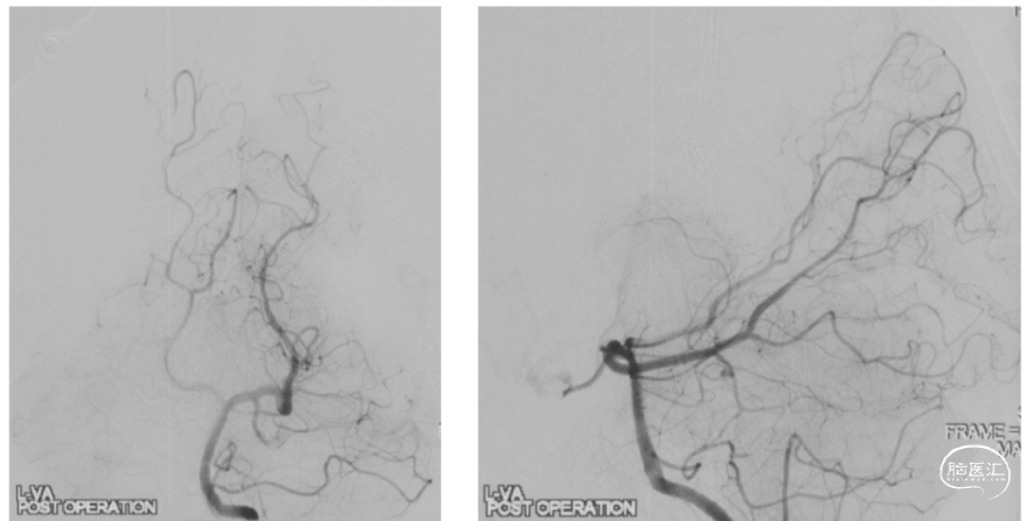

复查DSA:AVM切除术后即刻复查造影,显示AVM切除完整,无异常早显引流静脉

切除术中造影显示动静脉畸形切除完全